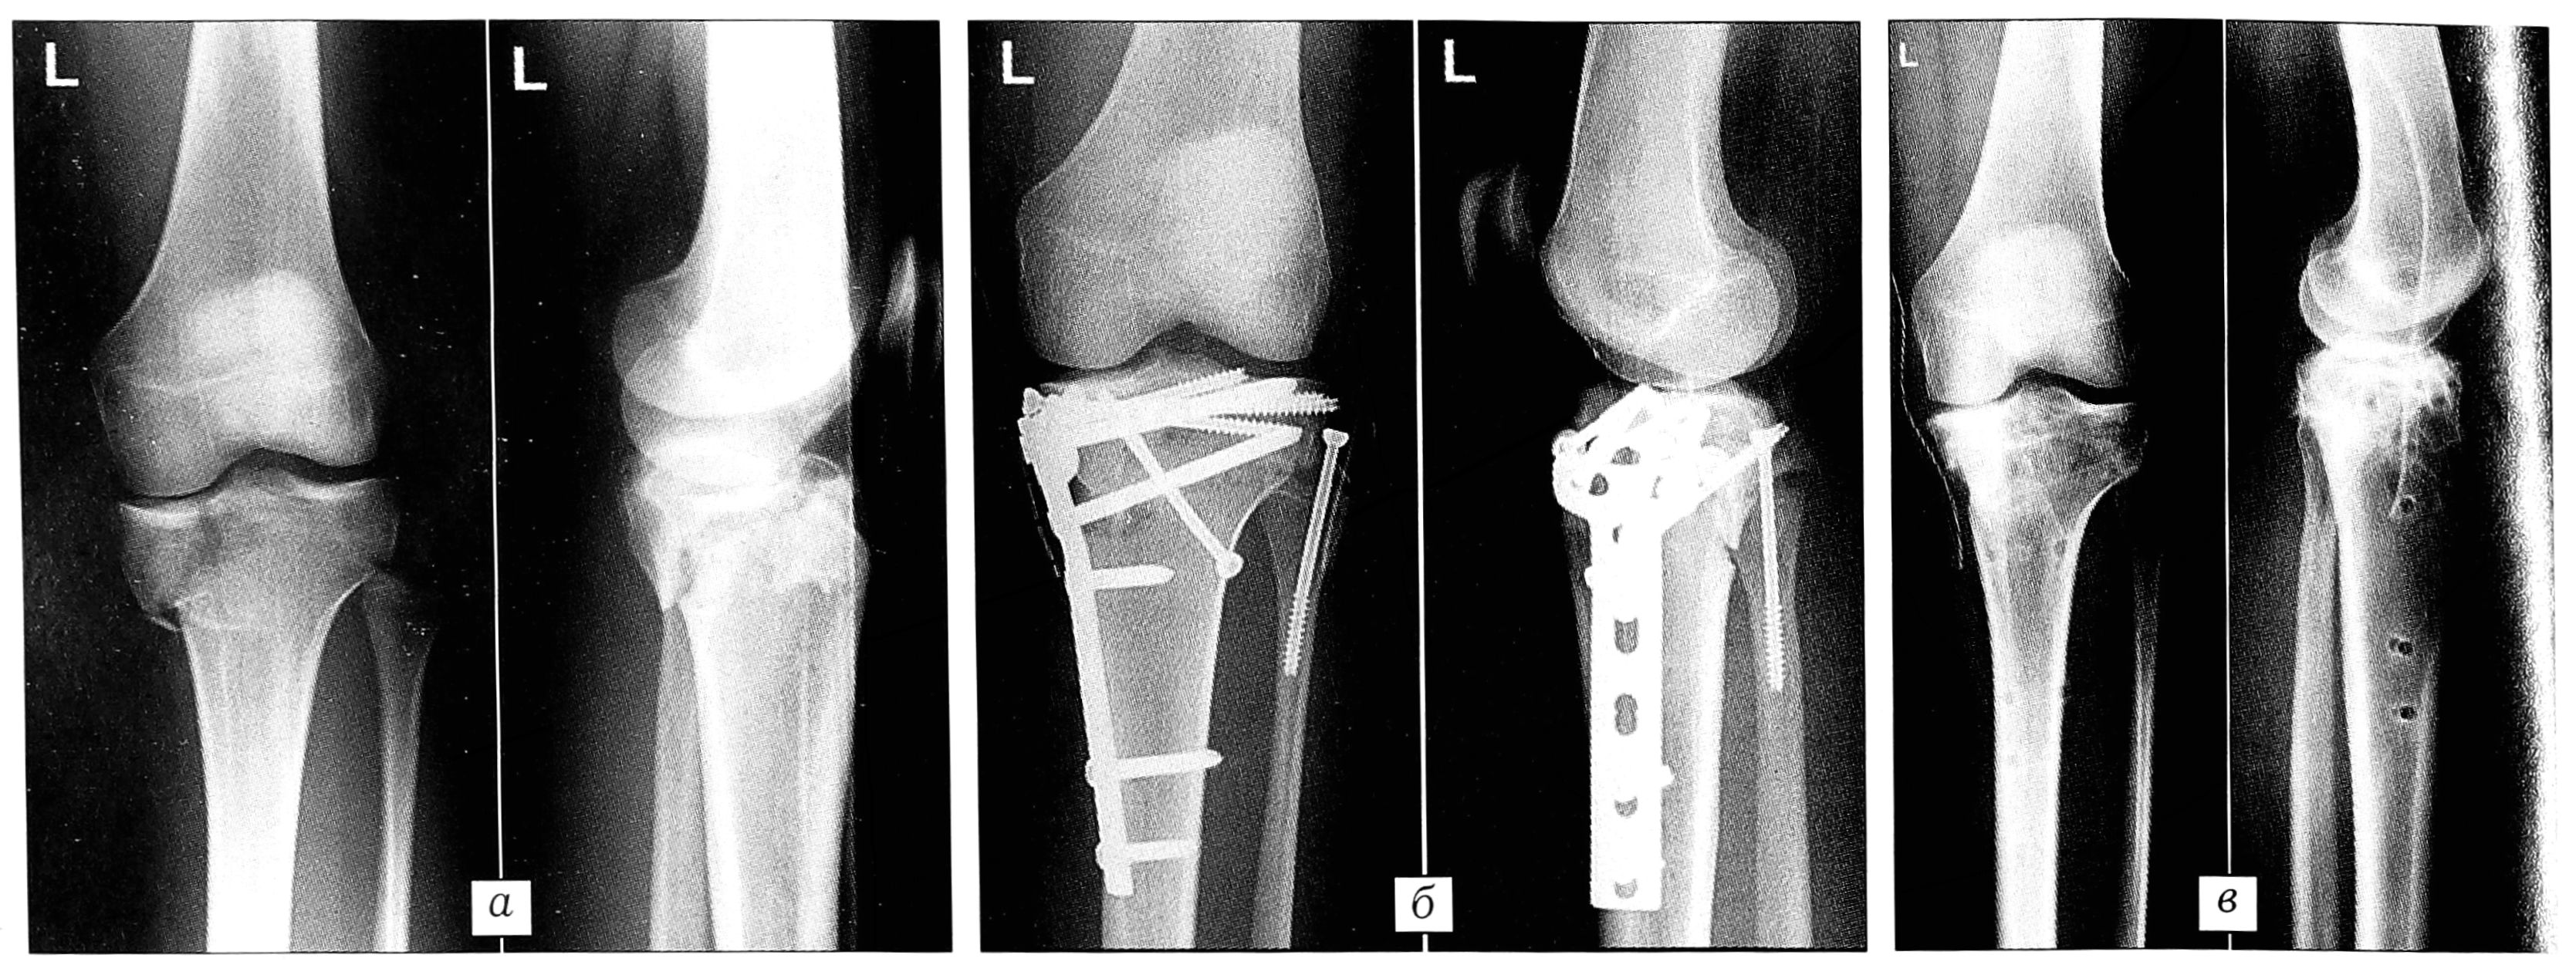

Рис. 9. Больной X. 19 лет. Травма получена при занятиях верховой ездой. а — при поступлении: перелом типа 41-С2.2 проксимального отдела большеберцовой кости; б — после анатомического восстановления суставной поверхности с использованием стягивающих винтов 4,5/5,0 мм применена LCP Т-образная пластина для «перемыкания» зоны многооскольчатого перелома в метафизарной области с фиксацией только блокирующимися винтами; в — через 1 год после операции имплантат удален (боль отсутствует, обем движений в суставе полный).